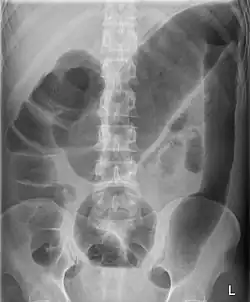

| Toxic megacolon associated with ulcerative colitis. | |

Toxic megacolon

Toxic megacolon is mainly seen in ulcerative colitis and pseudomembranous colitis, two chronic inflammations of the colon (and occasionally, in the other type of inflammatory bowel disease, Crohn's disease). Its mechanism is incompletely understood. It is probably due to excessive production of nitric oxide, at least in ulcerative colitis. The prevalence is about the same for both sexes.